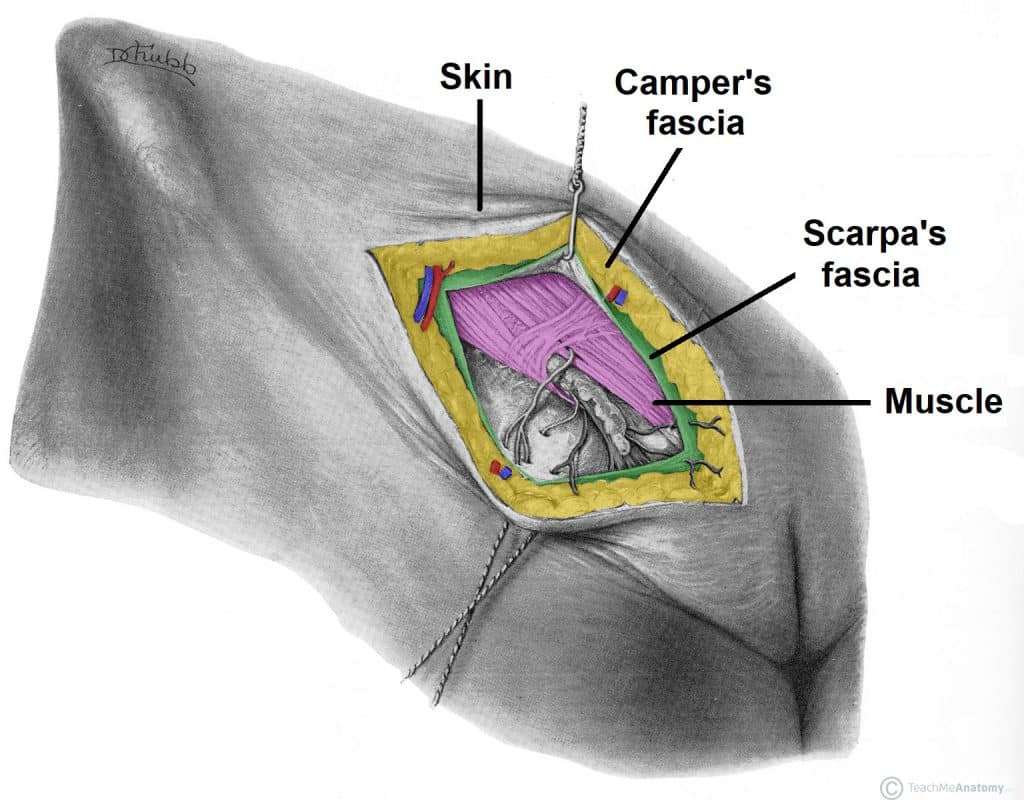

Superficial Fascia

- Layers:

- Fatty layer (Camper’s fascia)

- Membranous layer (Scarpa’s fascia)

- *Note from an M2: Know the different orders of fascia around different parts of the body, including groin area.